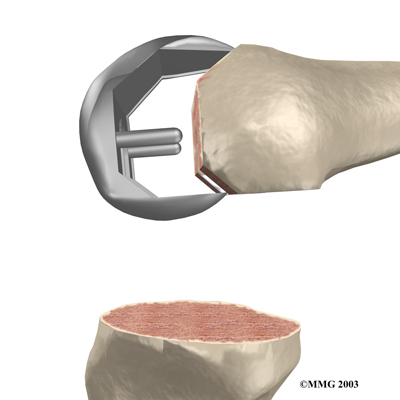

Then the artificial surface of the patella is removed.

The surgeon then sizes the patellar component andd puts it into place behind the patella. This piece is usually cemented in place.

Patellar Component

View animation of removing the patella and inserting the patellar component: